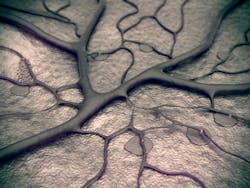

A team of researchers from Johns Hopkins Medicine (Baltimore, MD) has discovered a receptor on blood vessels that causes the vessel to relax in response to blue light, making it potentially useful in treating vascular diseases.

The researchers—led by senior author Dan Berkowitz, MD, a professor in the Department of Anesthesiology and Critical Care Medicine—looked for expression of a light receptor in the blood vessels of mice and discovered a receptor called melanopsin, or opsin 4—one of a group of non-image-forming light receptors. In mice without opsin 4, blood vessels did not relax in response to light.

Upon further study, Berkowitz and his team were able to determine the exact wavelength (455 nm) at which opsin 4 is activated and the blood vessel relaxation response is maximal. The scientists could use this wavelength-specific light to increase blood flow in the tails of normal mice, but not in the tails of mice that lacked expression of opsin 4.